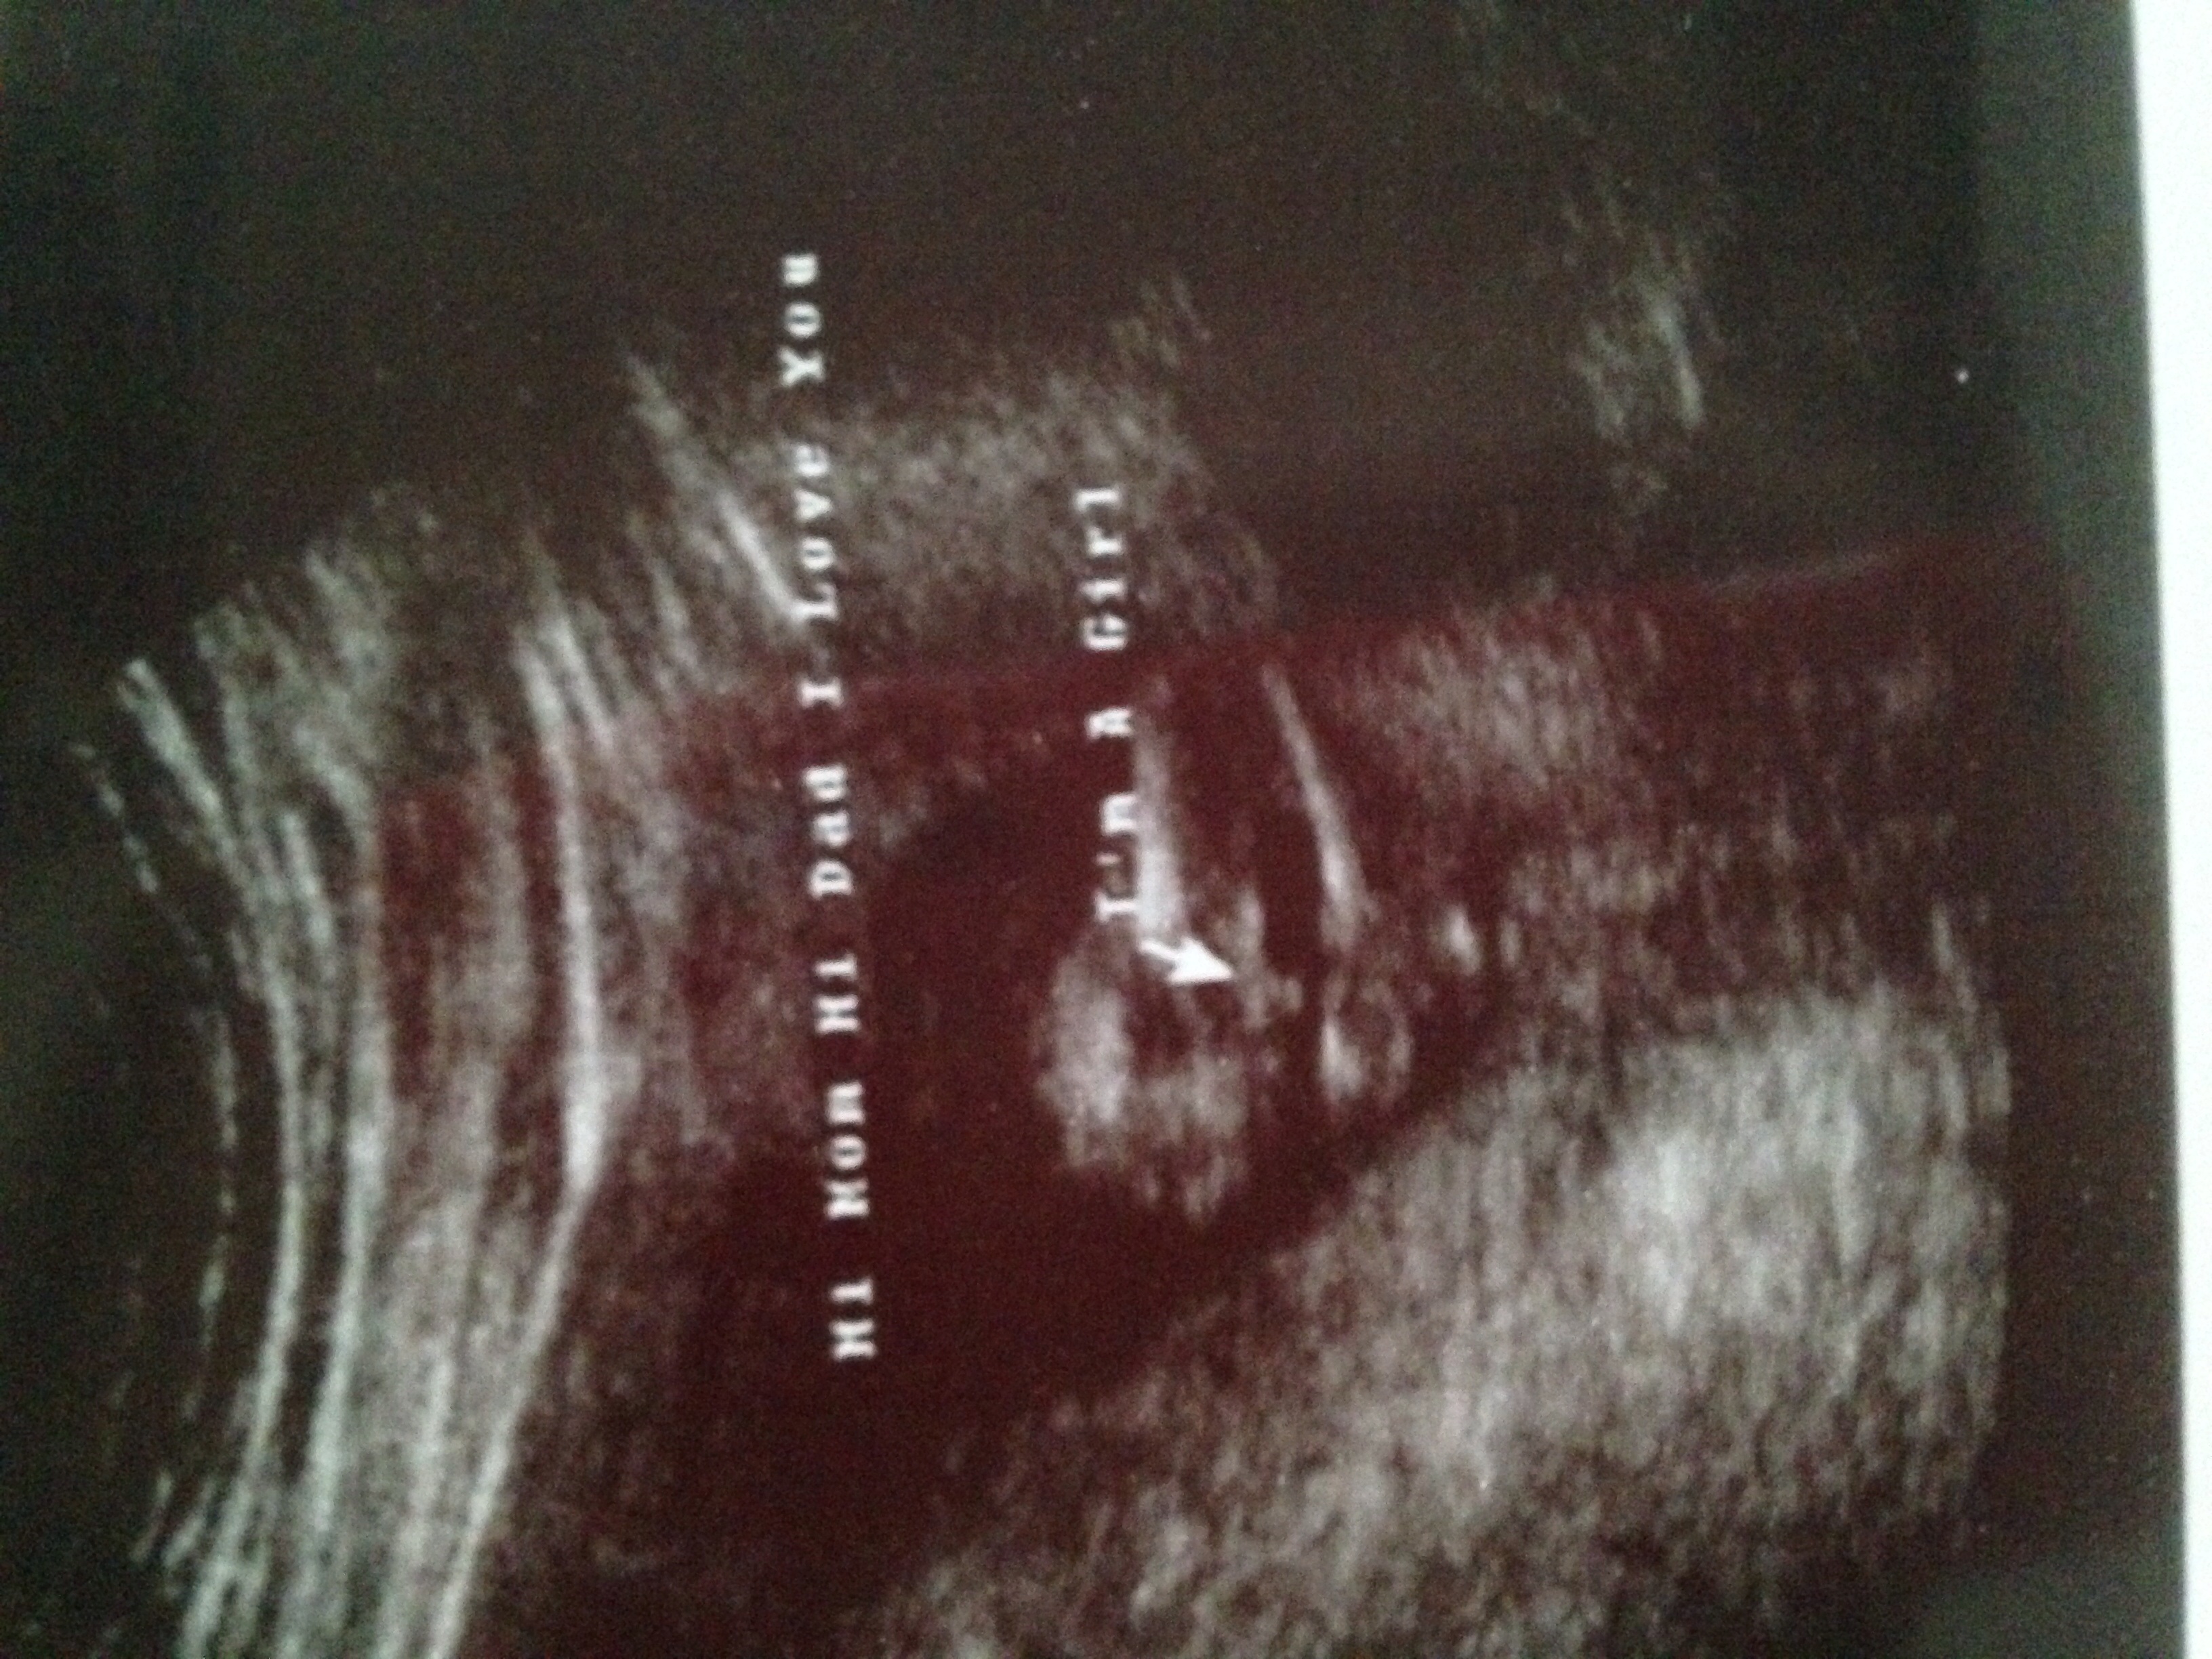

He's probably referring to the three lines that he is pointing too. That's what they look for on girls.

ETA: if you will google "girl ultrasound" (or something of the sort) then it will help you to see some larger images so you know what you are looking for.

Personally, I do see why the tech said "pretty sure girl," but only because I have been doing my own research on it. I don't really see this thread going over well, but since you asked WHY they said girl and not "what am I having?" I figured I would throw in my two cents.